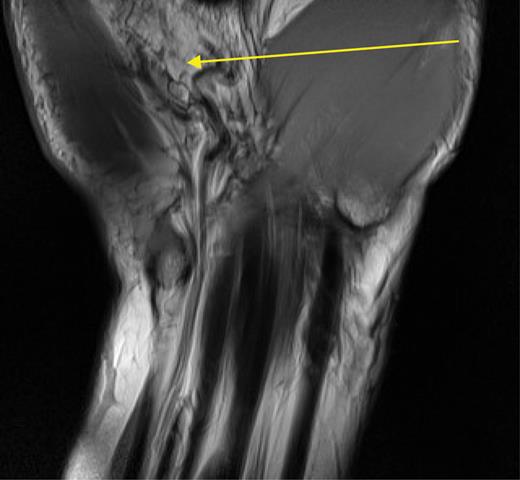

A T1-weighted and STIR (short T1 inversion recovery) MRI scan of the wrist, reconstructed in axial and coronal planes was performed (Fig. 1). This showed no obvious deformity in Guyon's canal and no abnormality along the ulnar nerve. However, it did demonstrate a multi-loculated ganglion along the volar aspect of the distal radius closely abutting the radio-carpal ligament and a fatty mass superficial to the roof of Guyon's canal. As the patient had persistent hand symptoms, we proceeded to surgically explore his wrist.

T1-weighted MRI scan of Guyon's canal. The arrow indicates the fatty mass reported as lying atop Guyon's canal.